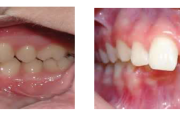

Turritavad ülemised lõikehambad.

prognaatne hambumus, ülemised eeshambad on ettepoole alumiste suhtes ja eest

ettepoole ulatuvad ülahambad